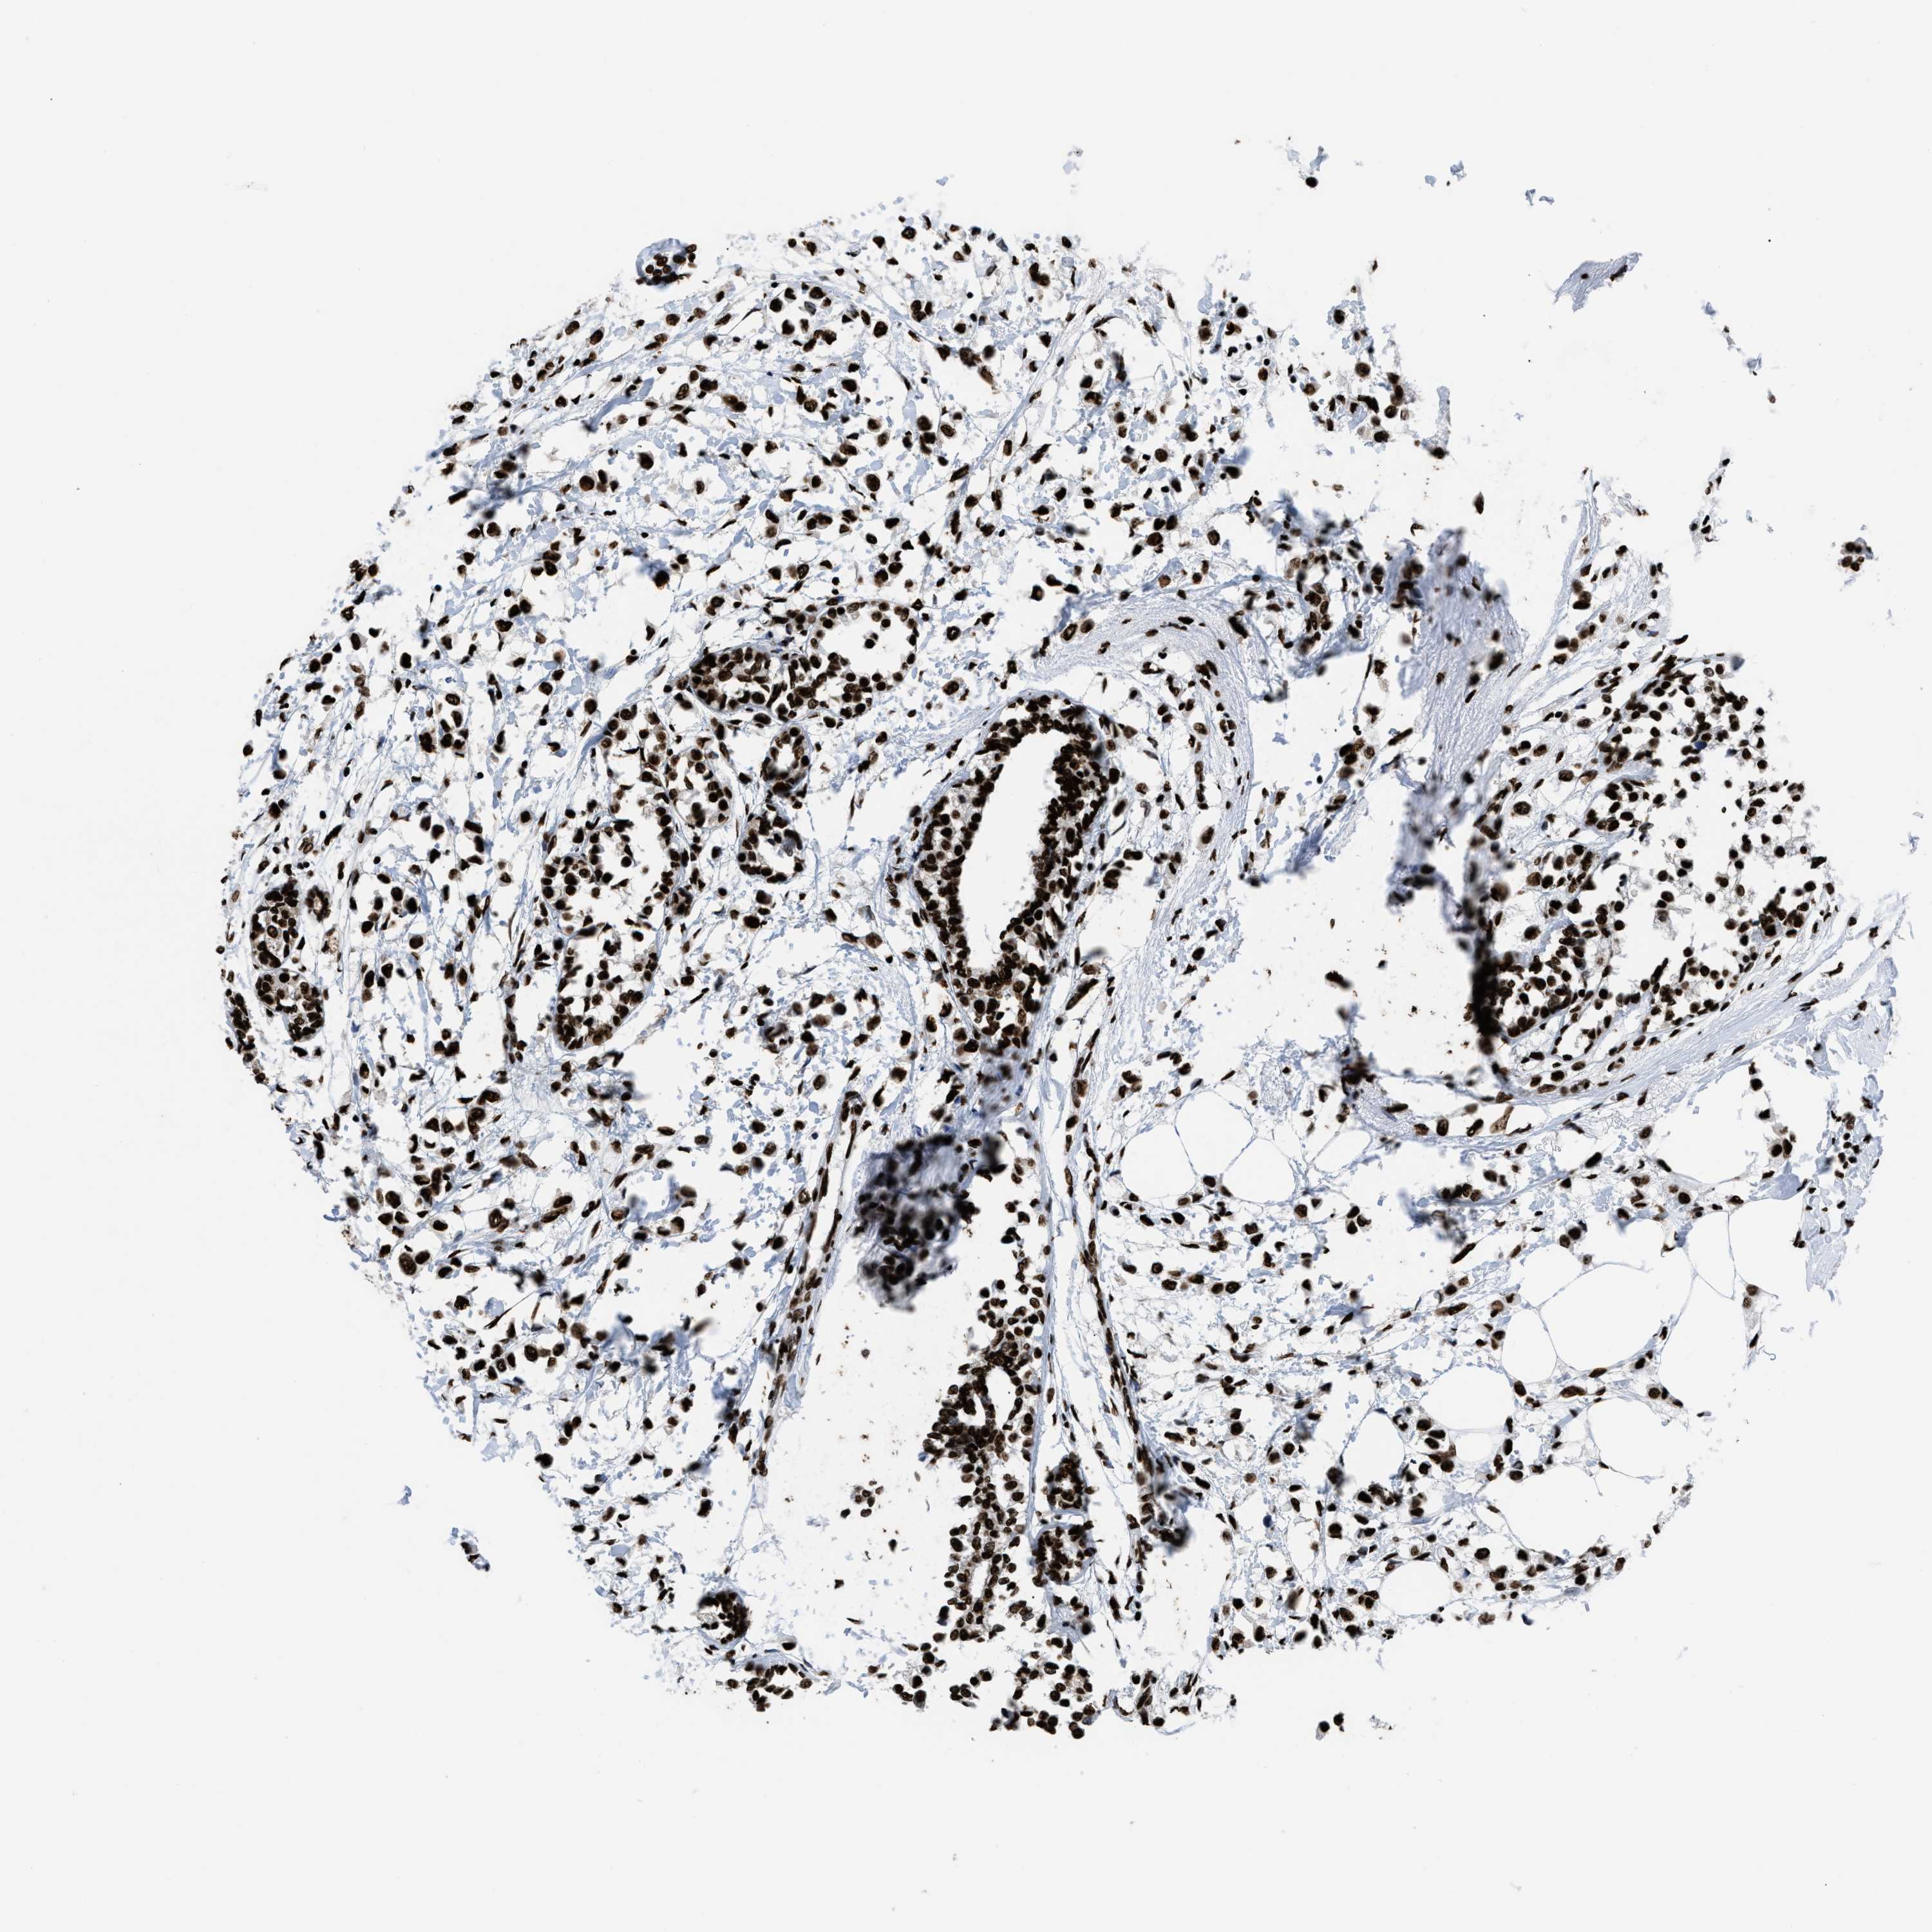

CANCER BREAST CANCER Show tissue menu

BRCA TCGA BRCA VALIDATION PROTEIN EXPRESSION

Breast cancer

Human cancer